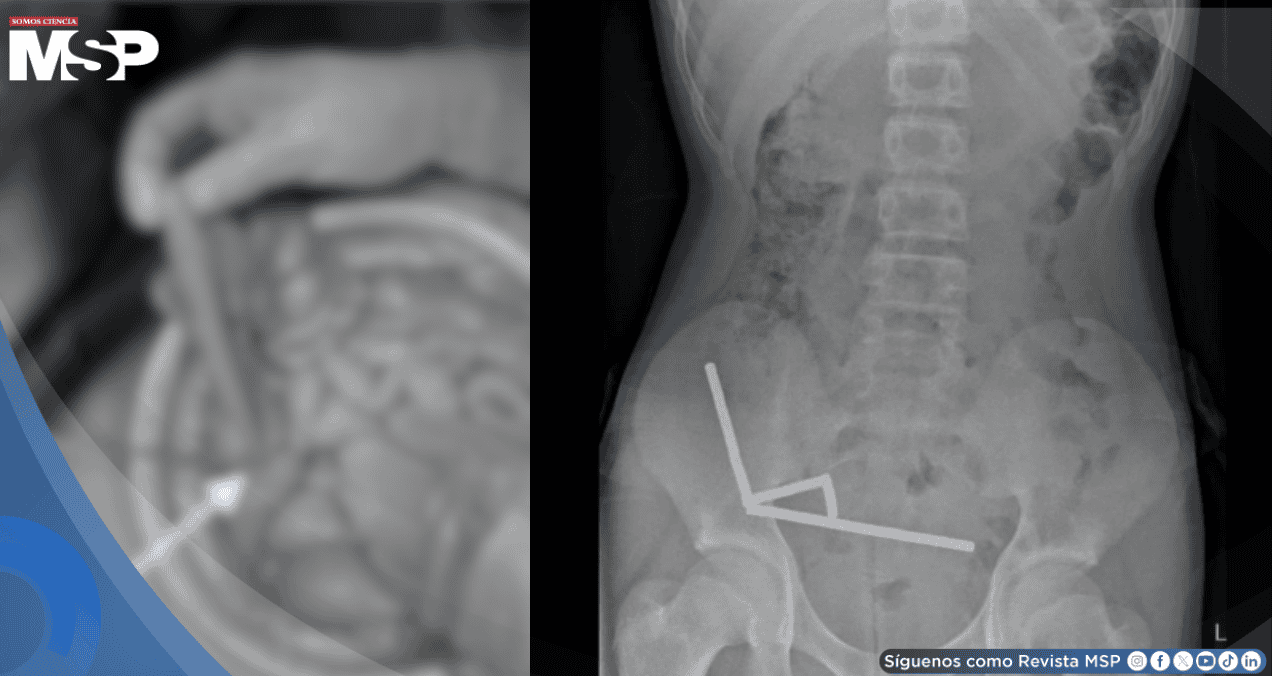

Durante la intervención quirúrgica, los médicos descubrieron una situación crítica en el sistema digestivo del adolescente.

Los pequeños imanes, de apenas 5 x 2 milímetros cada uno, se habían unido para formar cuatro cadenas dentro de sus intestinos. Esta agrupación magnética causó graves daños al tejido intestinal, obligando a los cirujanos no solo a extraer los imanes, sino también a remover secciones completas del intestino que habían resultado irreparablemente afectadas por la presión constante de los imanes unidos.